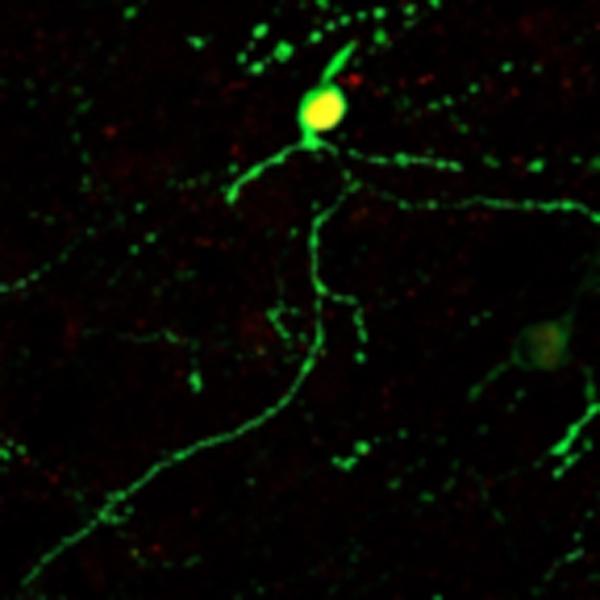

Neuroni convertiti via NeuroD1 (Fonte: Jinan University)

In questo lavoro, il prof. Chen e la sua squadra hanno ulteriormente esteso la loro tecnologia neuro-rigenerativa dal cervello al midollo spinale. Dimostrano per la prima volta che la sovra-espressione, attraverso un retrovirus, di NeuroD1 negli astrociti reattivi in divisione, può convertire con successo gli astrociti in neuroni nel midollo spinale ferito.

Il vantaggio dell'uso del retrovirus è che esprime solo il transgene, come il NeuroD1 qui, nelle cellule gliali in divisione, ma non nei neuroni che non si dividono, eliminando la possibilità di espressione diretta di NeuroD1 nei neuroni preesistenti. Per aumentare l'efficacia della conversione neuronale e preparare la strada a una futura applicazione traslazionale, Chen e il team hanno sviluppato ulteriormente il sistema virale adeno-associato (AAV) per portare NeuroD1 agli astrociti sia in divisione che non in divisione, sotto il controllo del promotore astrocitico GFAP e hanno confermato direttamente la conversione da astrocita a neurone nel midollo spinale.

Il vettore AAV è usato comunemente per la terapia genica a causa della sua immunogenicità relativamente bassa e dell'elevata efficienza di diffusione in vari tessuti, compreso il tessuto nervoso. È interessante notare che Chen e il team hanno scoperto che il NeuroD1 ha generato solo neuroni glutammatergici eccitanti, mentre l'aggiunta dell'altro fattore di trascrizione DLX2 ha aumentato significativamente la proporzione di neuroni gabaergici inibitori, indicando che l'uso di diverse combinazioni di fattori di trascrizione può generare diversi sottotipi di neuroni.